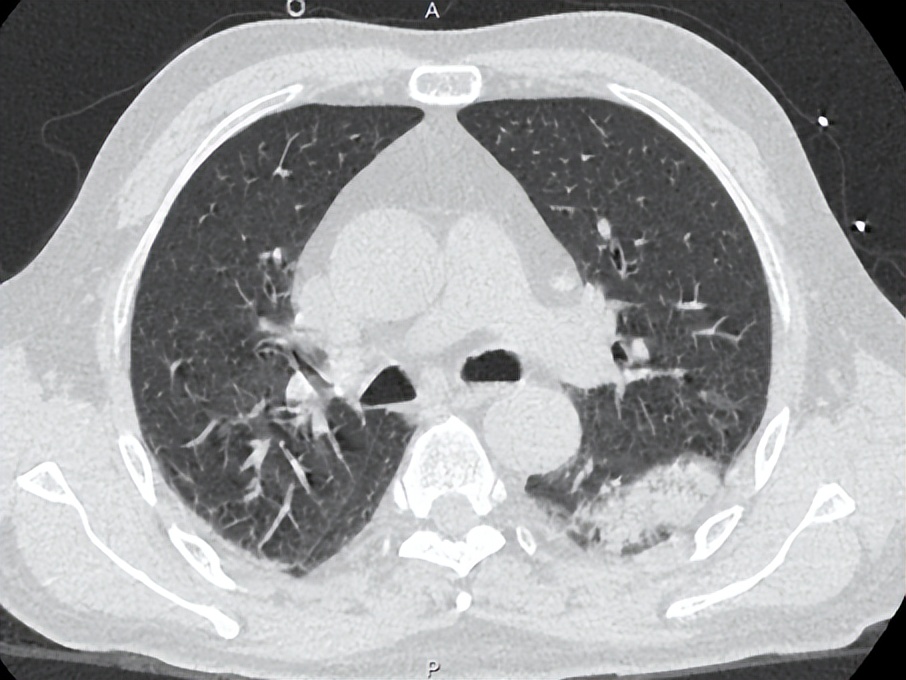

治疗后患者湿罗音减少,左肺可闻及Velcro啰音,7-6复查胸部CT如下:

考虑感染继发机化性肺炎,7.6加用泼尼松30mg po qd治疗机化性肺炎,继续多西环素0.1g bid治疗军团菌肺炎,并办理出院。

该患者的另一个临床特征是高PCT水平,据文献报道高PCT水平与需ICU治疗和高死亡率相关。 我们注意到,在病程中,PCT水平与体温未成平行下降关系,可能的原因为: 患者在入院初存在胃肠道症状和体征,包括腹泻、肠鸣音亢进。肠道作为细菌的蓄水池,此类患者可能存在肠道菌群移位。虽然没有相应的文献支持,我们在明确病原体为军团菌后,仍然将美平保留到7月2日,与多西环素重叠使用3天,直至PCT下降到安全范围。尽管在多西环素介入后, 6月30日床边胸片提示病灶较前明显增多,左肺大片浸润影,考虑到患者重症肺炎以及多个死亡相关预后因素存在,加用利福平5天联合抗军团菌。 患者在有效抗感染治疗基础上,7月6日复查胸部CT提示机化表现 ,氧合改善欠佳,给予短程激素应用,7月14日复查胸片提示病灶显著吸收。1个月后电话随访,患者原有咳嗽、气促等症状消失。